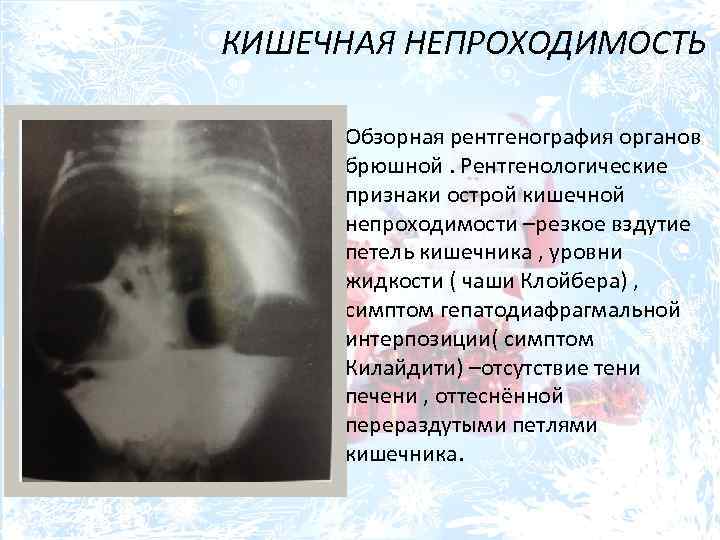

Иллюстрации и информация о симптомах острого кишечного непроходимости